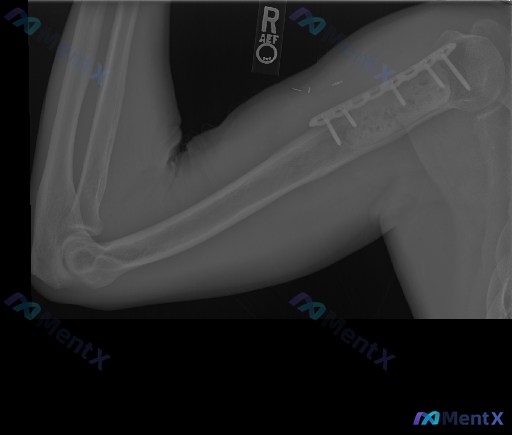

整理到一张右肱骨近端术后的侧位X光资料,先把影像里的客观发现列出来: 1. 肱骨近端有金属接骨板+多枚螺钉,位置在位; 2. 接骨板下方的骨组织区域骨密度增高、结构模糊; 3. 肱骨干及远端骨皮质连续,未见明确急性骨折线; 4. 肘关节对位正常,无明显脂肪垫征; 5. 软组织里有微小的金属密度影(考...